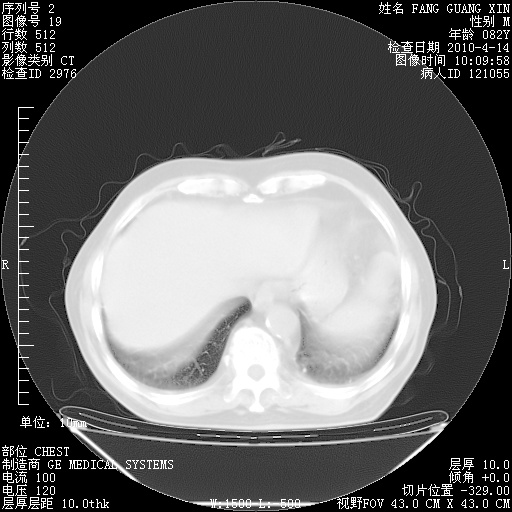

4月14日肺部CT

23.JPG

24.JPG

25.JPG

26.JPG

肺部CT平扫未见异常。